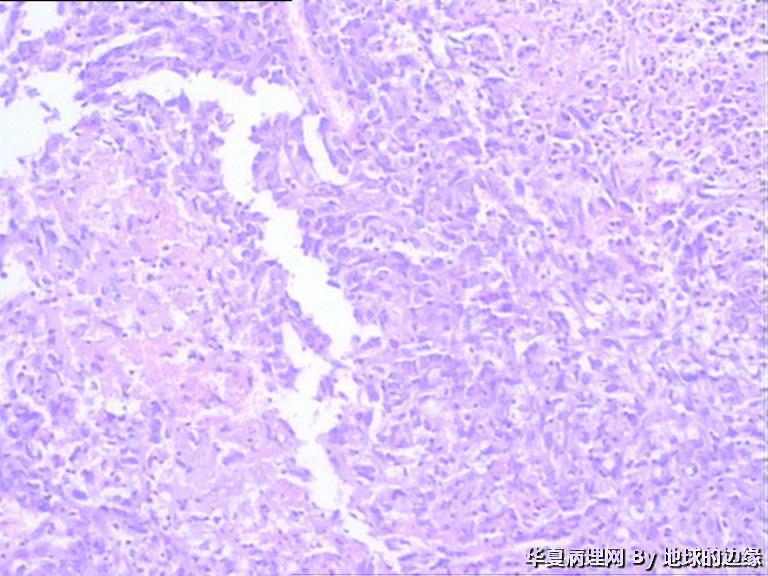

右肱骨肿瘤待查

病人女性,48岁

MRI示:右肱骨肿瘤待排,包块大小为10x8cm,活动度差,边界欠清,鱼肉组织(白色),肿块侵犯至骨外    组  织。

恶性。是转移还是原发,是骨肉瘤还是浆母?需要进一步资料并标记。

考虑肉瘤,转移癌也排除一下吧

目前Vimentin阳性,P53阳性,AFP,EMA,CK7,CK20,E-ca,CR,PLAP,CD99,ER,PR,CEA,均阴性,只是没做淋巴瘤这一套了